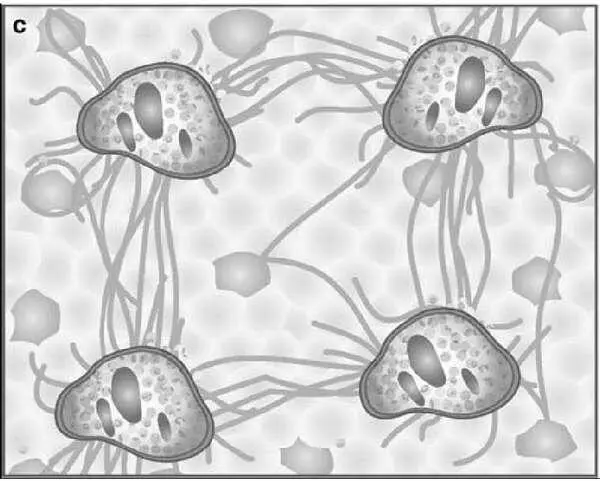

Рисунок 6 – Схемы формирования фиброза печени (по Batts KP, Ludwig J.)

На рис. 6 представлены диаграммы, отражающие последовательность развития фиброза в печени при гепатите. Представлены 4 стадии болезни печени: а – фиброз портальных трактов, b – септы, распространяющиеся от портальных трактов и местами соединяющие их; c – трансформация в цирроз печени, когда в некоторых участках исследуемого образца отмечаются формирующиеся узлы регенерации; d – окончательно сформированный цирроз печени.